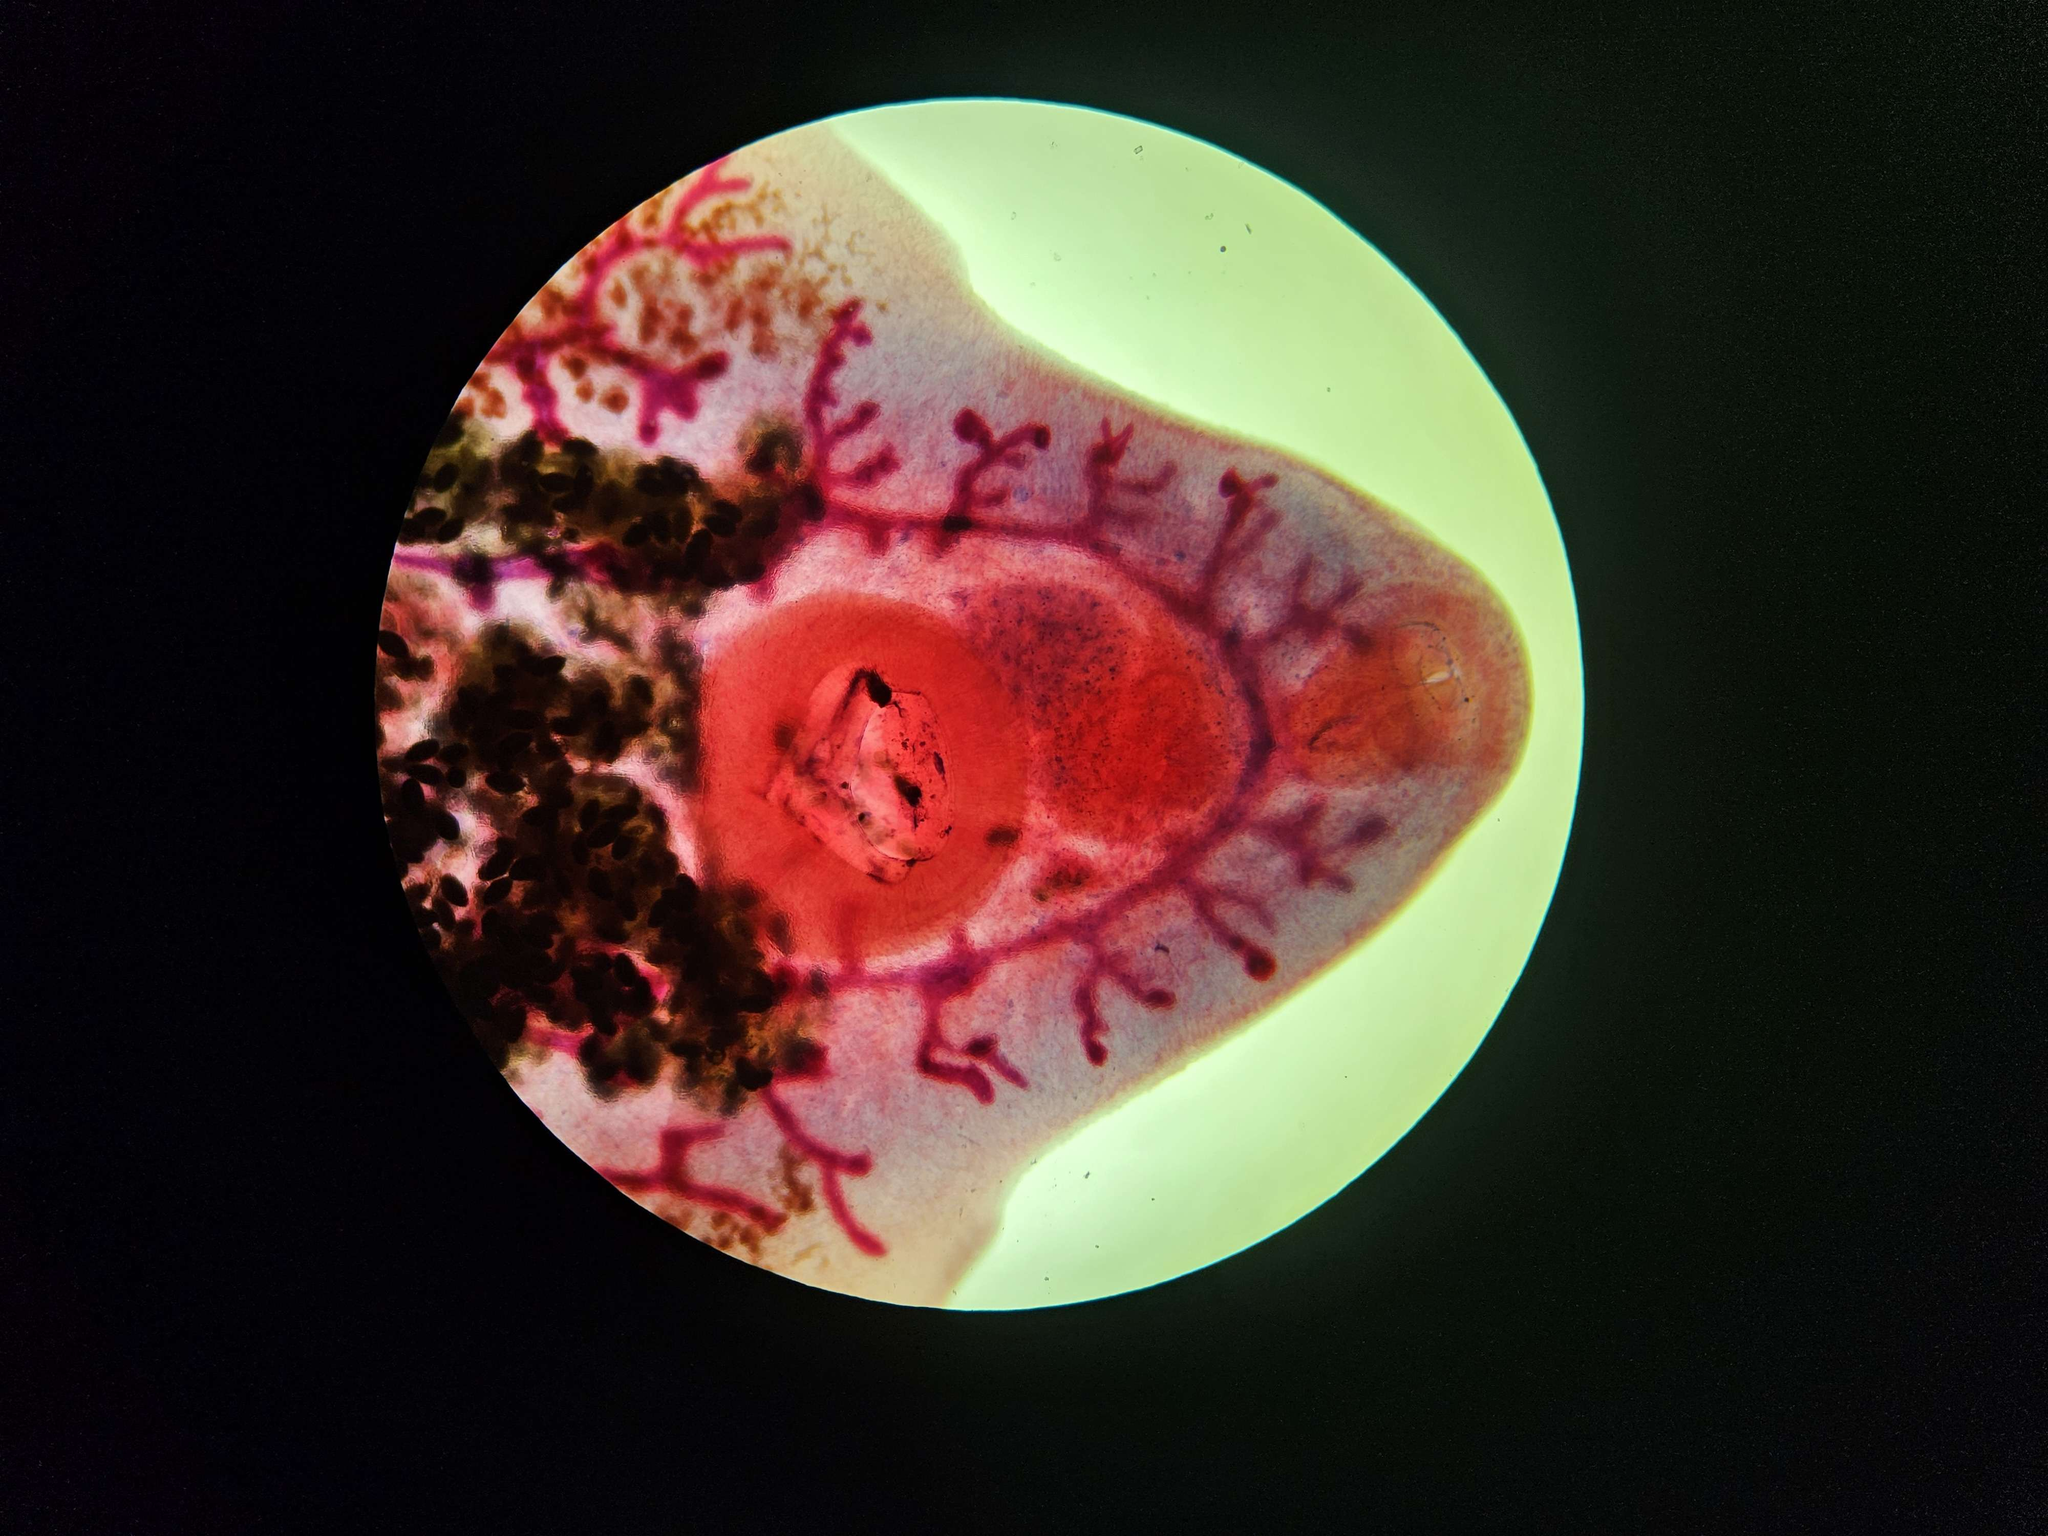

🩸🤖 Plasmodium sp. (śledziona - malaria melanemia)

🧩🦠 Cechy charakterystyczne:

🔴🟡🟢️🟤 - złogi hemosyderyny.

😷❓ Parazytoza: Malaria